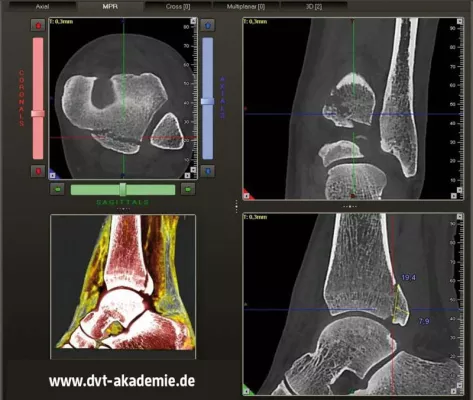

DVT-Röntgen in der Orthopädie - NEUE KURSE 2019/2020

Krefeld / OKTOBER 2019 - DVT Akademie® stellt neue DVT-3D-Röntgenkurse für Humanmedizin vor und gibt das neue Kursprogramm für Zahnmedizin, MKG-Chirurgie und HNO-Heilkunde 2020 bekannt. Die aus der MKG-Chirurgie und HNO-Heilkunden bekannte digitale Volumentomografie, eine strahlungsarme Alternative zur klassische Computertomografie, hielt im laufenden Jahr 2019 mehr und mehr Einzug in die Fachgebiete der Orthopädie und Chirurgie. Neben der reduzierten Strahlenbelastung und der hohen Abbildungsleistung von bis zu 0,075 mm Voxelgröße sind dig…